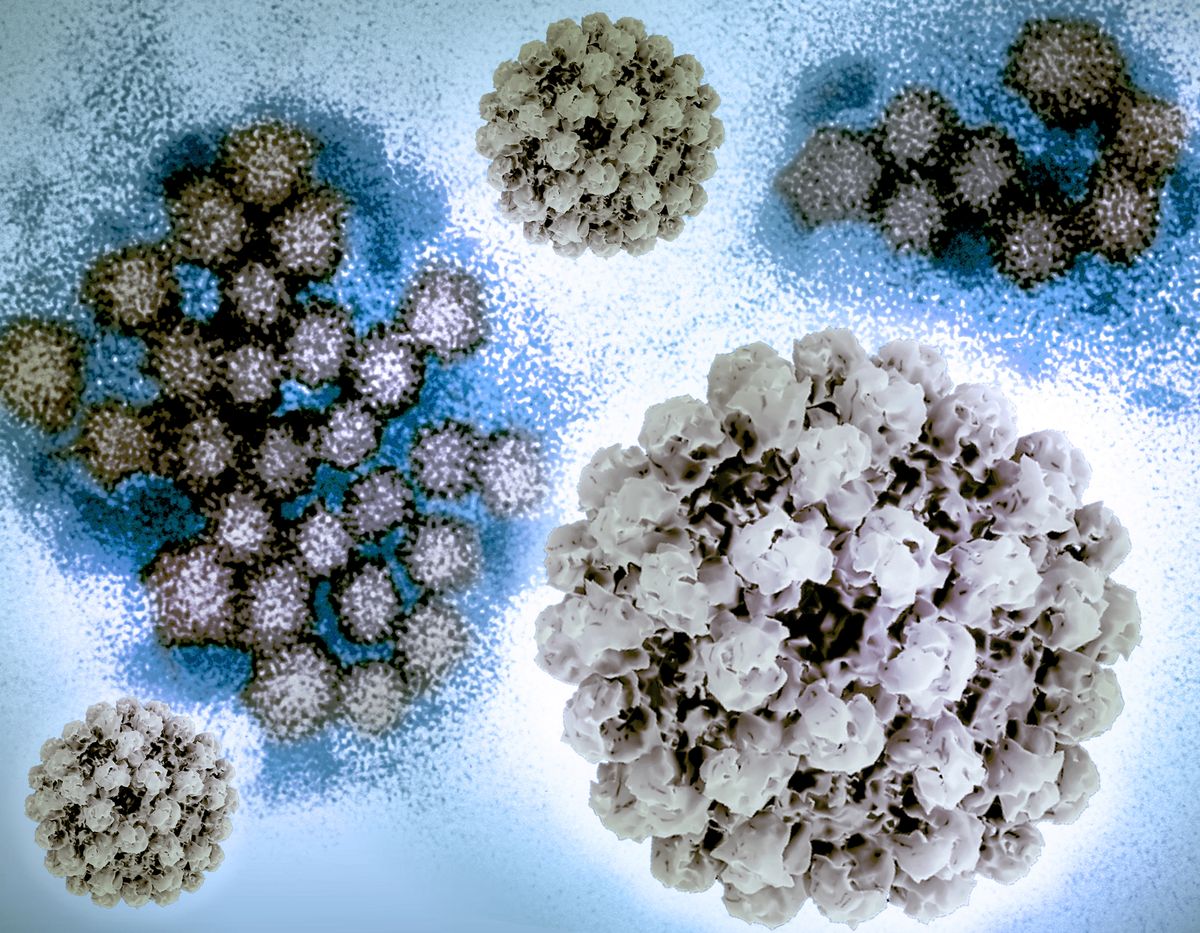

One such waste product is amyloid beta (Aβ) protein. Aβ that accumulates in the brain can form clumps called plaques. These, along with tangles of tau protein found in neurons (brain cells), are a hallmark of Alzheimer’s disease, the most common type of dementia.

In humans and mice, studies have shown that levels of Aβ detected in the cerebrospinal fluid increase when awake and then rapidly fall during sleep.